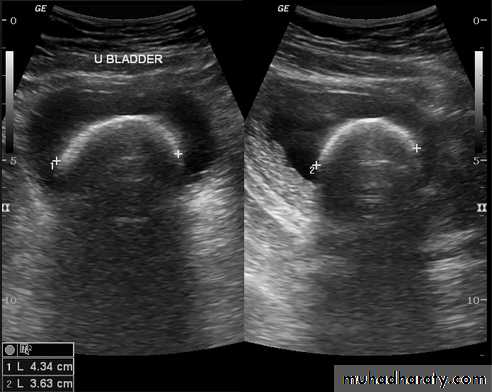

Urinary tract US

Renal ultrasound is a simple noninvasive examination .

The kidney is bean shaped and has bright central echoes because of the fat surrounding the collecting system.

Ultrasound is typically ordered to exclude , stones , hydronephrosis or to evaluate renal size or suspected renal cysts .

Normal renal ultrasound.

A longitudinal view of the right kidney was obtained by passing the sound beam through the right lobe of the liver. The kidney is seen behind this, outlined by the markers. The central bright echoes in the kidney are due to fat around the collecting system.